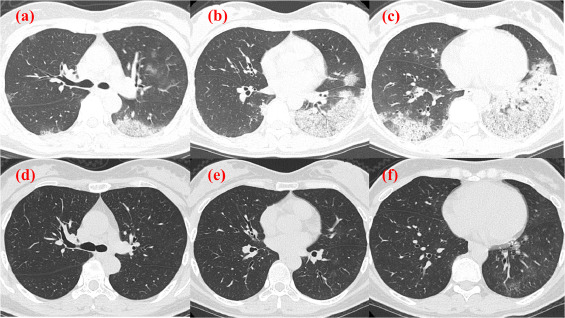

患者因严重的食欲不振和恶心入院。来我院就诊时患者体温38.5℃;血压,121/60 mmHg;呼吸频率,20次/分;室内空气下氧饱和度(SpO2)为95%;胸部听诊可闻及粗湿啰音 。HRCT显示右肺上叶弥漫性磨玻璃影(ground-glass opacity,GGO),左舌叶和双侧肺下叶实变,伴有左舌叶和双侧下叶实变伴支气管充气征(图1a-c)。

图1 a–f入院时(a–c)和出院后18天(d–f)的计算机断层扫描。

a, c.左肺下叶大叶性肺炎伴支气管周围GGOs,右下叶和左舌叶实变。

b.大叶性肺炎伴左肺下叶支气管充气征。

d, e.GGO和实变均消失。

f.左肺下叶大叶性肺炎消失,但支气管周围ggo仍存在。

而患者的4岁女儿在7天前出现发热,并被诊断为hMPV感染。本例诊断患者为hMPV引起的肺炎,并停用LSFX。停用抗生素后,腹泻和咳嗽等症状逐渐改善,入院时明显的轻度血小板减少症也逐渐改善,因此患者在住院第6天出院回家。出院后症状持续改善。出院后第18天的HRCT显示少量残余的中央混浊,但有消退趋势(图1d–f)。